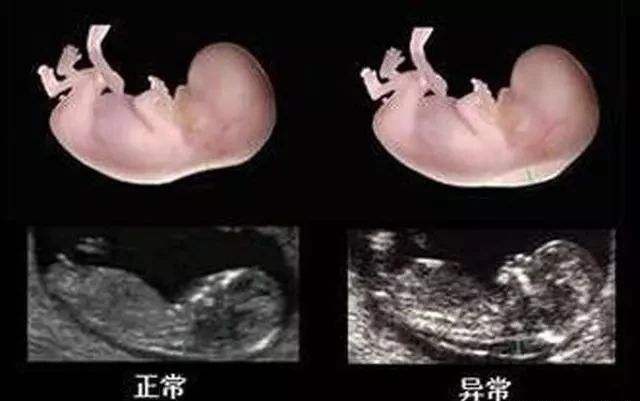

NT检查,是一个产检项目的简称,全称是:nuchal translucency,指的是“颈项透明层”,但并不是看孕妇的脖子,而是针对胎儿的检查,通过B超测算出肚子里胎儿的颈椎厚度(颈椎水平矢关切面皮肤至皮下软组织之间的最大厚度),它是整个孕期产检项目中重要的一项。

前面也说了,NT检查主要是检测胎儿颈部透明层的厚度,然后根据这个厚度数值评估胎儿的发育情况,主要是为了初筛查“是否有患唐氏综合征的可能”,算是孕期第一次排畸检查。

NT检查的临界值规定,在不同医院标准会有差异,的确有些医院是2.5mm为临界值,也有些是3.0mm或3.5mm。具体的以当地医院的诊断标准为诊断依据就好,如果以2.5mm为临界值,那只要测出来的厚度大于3mm就提示胎儿患唐氏症的风险较高,而且数值越大,风险越大。

唐氏儿NT值大多数不正常,但NT值高不一定就是唐氏儿,只是说明胎儿有患“唐氏综合征”的风险大,概率在60%-70%,需要做进一步检查确认和排查。

生活中,不少NT值异常的胎儿出生后也都是健康的宝宝,可也还有少数NT异常的胎儿出生后是唐氏患儿,因此孕妈们不能因为这个患病概率小就认为NT检查没有必要做,当然结果异常也不一定就说明胎儿是“唐氏儿”,需要继续做其他检查(羊水穿刺、绒毛活检、无创等)进一步确认。

其次,做B超查出来的“颈后透明带厚度”的准确度由很多因素决定,如B超医生的水平、扫描仪的精确度等,而且如果取的不是正矢位,也会有误差,因此检查结果并不能保证100%准确。

第三,NT检查属于早期筛查,并非确诊检查,查出来的NT增厚,意味着胎儿异常风险增加,但不一定代表胎儿不好,另外,NT增厚与跟染色体也有很大关系,也可以做染色体检查进行排查,如无创和羊穿。

最后,NT增厚还可能有心脏缺陷风险,因而建议在做排畸B超时要注意排查下胎儿心脏是否有问题。